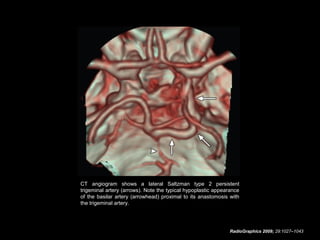

CT angiogram shows a lateral Saltzman type 2 persistent

trigeminal artery (arrows). Note the typical hypoplastic appearance

of the basilar artery (arrowhead) proximal to its anastomosis with

the trigeminal artery.

CT angiogram showsa lateral Saltzman type 2 persistent trigeminal artery (arrows). Note the typical hypoplastic appearance of the basilar artery (arrowhead) proximal to its anastomosis with the trigeminal artery. RadioGraphics 2009; 29:1027–1043